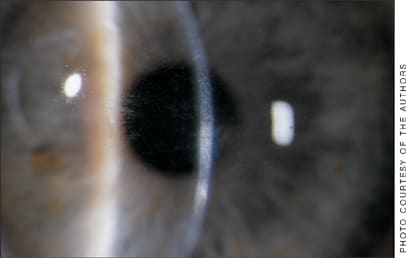

A patient 1 day following LASIK presented with pain, decreased vision and focal clustered infiltrates, some extending beyond the flap margin. These are warning signs of early LASIK-associated microbial keratitis, requiring flap lift, culture and scraping, antibiotic irrigation of the interface and intensive antibiotic treatment.